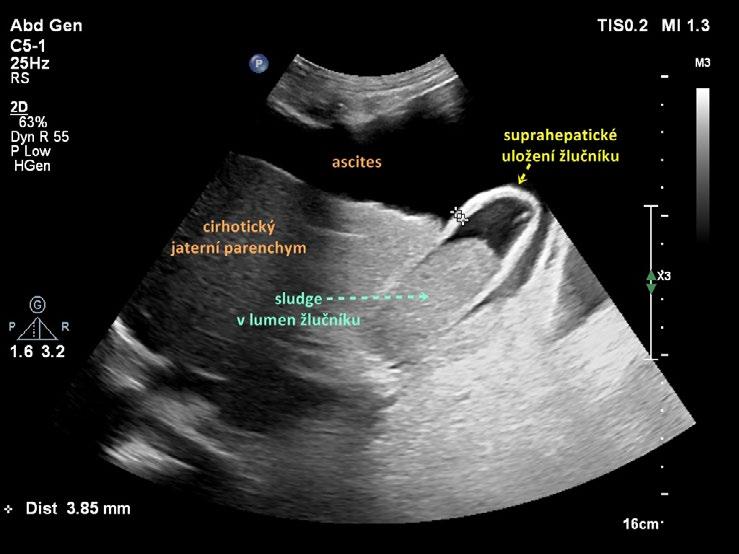

■ suprahepaticky, kdy je žlučník vytlačen mezi játra a bránici. Bývá tomu tak u pacientů s atrofickou cirhózou jater a ascitem (obr. 1.12) nebo u pacientů s emfyzémem plic;

atonii a hydrops. Zvětšený, atonický žlučník může dosahovat velikosti až 15 × 6 cm. Atonický žlučník je kompresibilní, nebolestivý a zpravidla nehmatný. Bývá přítomen při déletrvající absenci příjmu potravy (totální parenterální výživa, hladovění), u diabetiků, cirhotiků nebo u starých osob. Při hydropsu je žlučník zvětšený (zpravidla nad 10 × 4 cm), zaoblený, napjatý a nekompresibilní. Palpačně je elastický a (na rozdíl od akutní cholecystitidy) nebolestivý. Nejčastější příčinou hydropsu je blokáda krčku žlučníku (nejčastěji konkrementem). Hydropicky zvětšený žlučník může být první známkou extrahepatální cholestázy při blokádě v oblasti hlavy pankreatu, Vaterovy papily nebo společného žlučovodu pod odstupem ductus cysticus. Hydrops žlučníku s ikterem při blokádě distálního choledochu tumorem hlavy pankreatu je klinicky znám jako Courvoisierův příznak.